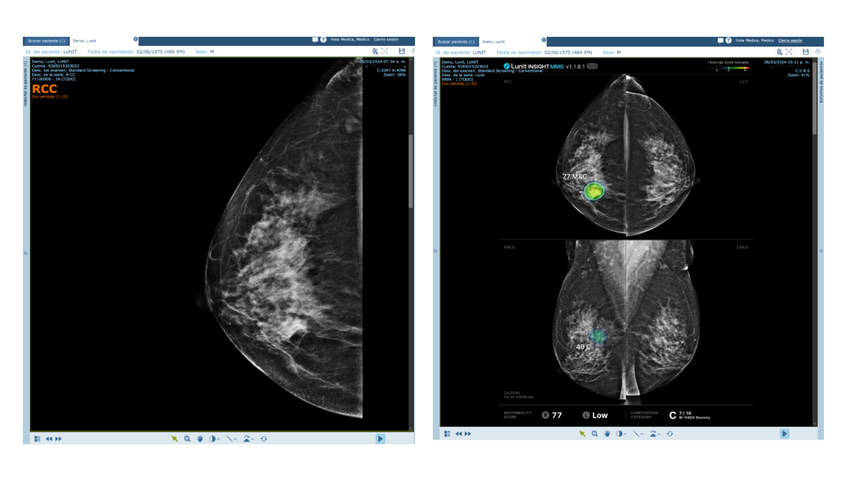

Pero la innovación va más allá. En alianza con Lunit, referente mundial en inteligencia artificial aplicada a radiología, Maxia ha incorporado algoritmos avanzados que permiten la detección temprana de cáncer de mama y hasta 11 patologías asociadas a problemas pulmonares. Estos modelos analizan imágenes médicas con un nivel de precisión capaz de identificar lesiones que podrían pasar inadvertidas en etapas iniciales, cuando el tratamiento es más efectivo y menos invasivo.

- Empodera a los médicos, proporcionándoles herramientas de apoyo para diagnósticos más rápidos y certeros.

- Optimiza recursos hospitalarios, priorizando casos según el nivel de riesgo.

- Previene complicaciones al permitir intervenciones tempranas que mejoran el pronóstico y reducen costos de tratamiento.